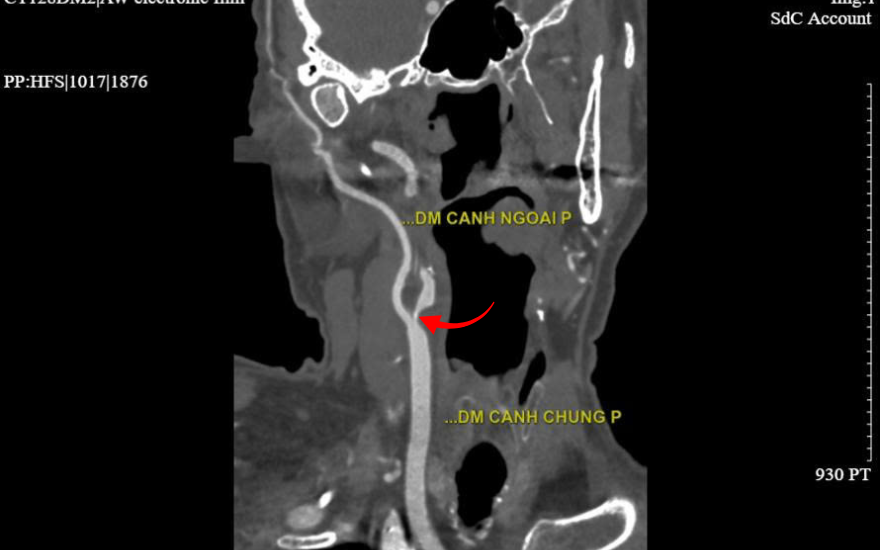

Ngay khi tiếp nhận ca bệnh, ThS.BSNT Cao Mạnh Hưng - Khoa Tim mạch - Tim mạch can thiệp, BVĐK Hồng Ngọc - Phúc Trường Minh đã nhận định ông Halpern có biểu hiện điển hình của cơn thiếu máu não thoáng qua, tiềm ẩn nguy cơ đột quỵ rất cao. Các kết quả thăm dò cận lâm sàng sau đó cho thấy động mạch cảnh trong bên phải của người bệnh bị hẹp rất khít (>90%) ngay từ lỗ vào, kèm theo nhiều mảng xơ vữa. Ngoài ra, hệ mạch vành cũng ghi nhận hẹp trên 90% tại động mạch liên thất trước.

Vị trí hẹp mạch cảnh trên hình ảnh chụp CT 2560 lát cắt

Hẹp động mạch cảnh khiến dòng máu lên não bị giảm sút hoặc tắc nghẽn chính là nguyên nhân gây ra những triệu chứng nguy hiểm mà ông Halpern gặp phải. Bác sĩ Hưng cảnh báo: “Nếu lòng mạch không được tái thông kịp thời, người bệnh có thể đối mặt với cơn tai biến mạch máu não cùng những di chứng nặng nề như liệt, rối loạn ngôn ngữ, sa sút trí tuệ, thậm chí đe dọa tính mạng”.